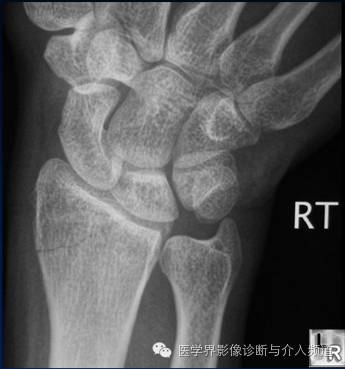

6、Colles 骨折

桡骨远端横形骨折。骨折线位于干骺端,邻近关节,远折端向背侧移位,断端向掌侧成角,通常伴尺骨茎突骨折。受伤机制为摔倒时候手撑地成过伸状。

7、Smith骨折

桡骨远端横形骨折,又称反Colles骨折。骨折线位于干骺端,邻近关节,远折端向掌侧移位,断端向背侧成角,通常伴茎突骨折。受伤机制摔倒时候手撑地呈过屈状。